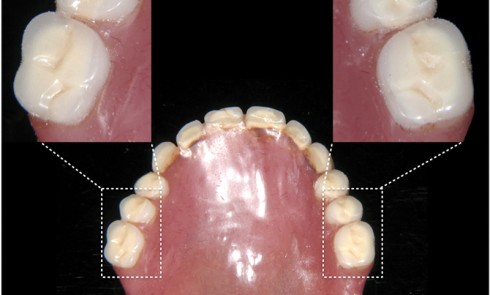

Article réservé à nos abonnés Prothèse complète implanto-portée: caractérisation de la fausse gencive en résine composite

Le succès d’une restauration prothétique, qu’elle soit fixe ou amovible, unitaire ou multiple, repose sur des exigences fonctionnelles mais aussi,...